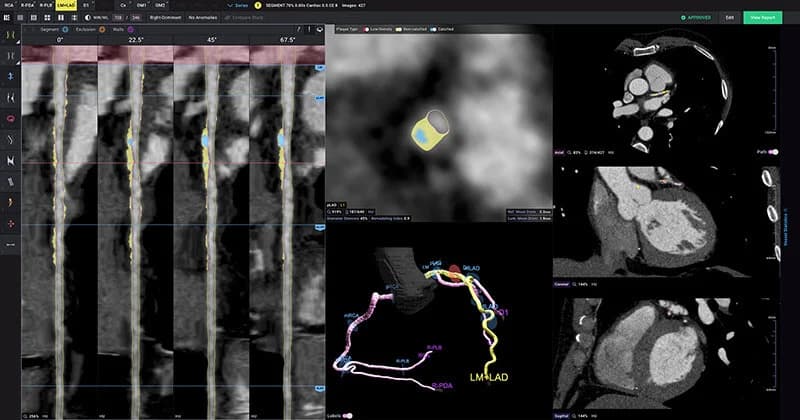

A Cleerly heart scan is not a separate scan. It is an AI-powered plaque analysis that runs on the coronary CT angiogram data. You still get the same CT scan at an imaging center. The difference is what happens after: instead of only having a radiologist review your images, the images are also sent through Cleerly's FDA-cleared algorithms for a detailed plaque analysis.

Cleerly's software maps your coronary arteries in 3D, then identifies, measures, and categorizes every piece of plaque it finds. The result is a color-coded report showing exactly where plaque sits, how much there is, and what type it is: calcified (stable), soft (intermediate risk) and vulnerable (high risk).

Plaque type matters because not all plaque is equally dangerous. Hard, calcified plaque is generally stable. Soft plaque is generally more risky and more likely to rupture and cause a heart attack. A subtype of it, called vulnerable or thin cap plaque, is even more risky. A standard CT angiogram report notes whether plaque is present and estimates blockage severity, but it does not precisely measure plaque volume or reliably quantify different plaque types. That is where Cleerly adds the most value.